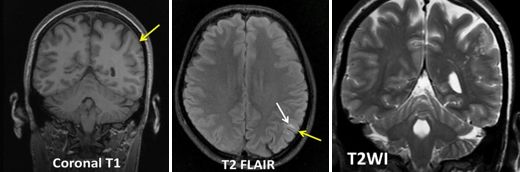

患者,12岁,反复癫痫发作,头MRI如下:

答案:大脑多结节和空泡状神经元肿瘤( MVNT )

MVNT是一种良性浅表性神经元瘤,多表现为长期的癫痫发作。该肿瘤2013年被首次报道。临床上,MVNT多为偶然发现,患者多表现为长期的癫痫发作。这个病例好多老师不认识,其影像特点是MRI表现为皮层下小团簇状、囊性、结节性病变,T2/FLAIR呈高信号(像很多泡泡)(T1可呈略低信号)。病变多位于深部皮层带和浅表皮层下白质,多无明显强化,可有点状轻度强化,无扩散受限及磁敏感效应。病变很少进展或体积变大,多无占位效应及瘤周水肿。故该病多建议进行观察随访,不建议进行干预。鉴别诊断有局灶性皮质发育不良、瘤样血管间隙、胚胎发育不良性神经上皮肿瘤(DNET)、毛细胞性星形细胞瘤、节细胞胶质瘤、多形性黄色星形细胞瘤等。容易误诊为DNET,DNET为边界清楚、楔形囊泡状皮质内肿块,常伴有皮质发育不良。DNET也多见于年轻患者,生长也非常缓慢,表现为难治性癫痫发作。颞叶(常常是杏仁核和海马区)是最常见的发病部位,其次为额叶,多呈边界清楚的三角形。